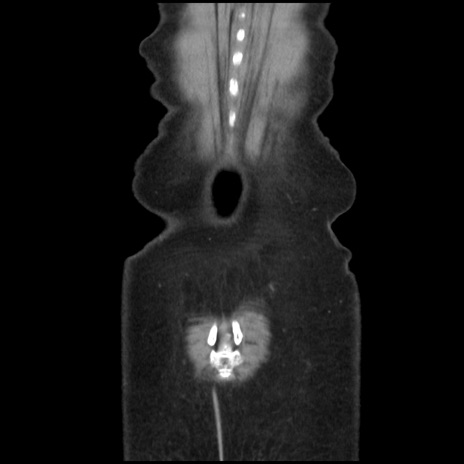

矢状断像

【症例】40歳代 女性

【主訴】上腹部痛、嘔気・嘔吐

【現病歴】約9時間前頃から急に上腹部痛、嘔気、嘔吐が出現。改善しないため救急要請。

【既往歴】子宮頚癌(広汎子宮全摘術、放射線療法)、腸閉塞

【身体所見】腹部:平坦、軟、腸雑音亢進、上腹部を中心に腹部全体に圧痛あり。

【データ】WBC 8400、CRP 0.03